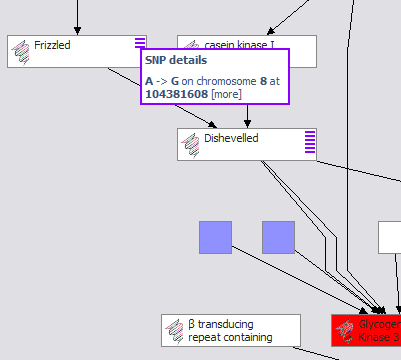

The demonstration focuses on an investigation into the therapeutic value of GSK3beta (glycogen synthase kinase 3 beta), a regulatory enzyme associated with multiple diseases, including diabetes type 2 as well as Alzheimer’s. Several screened compounds are known antagonists of GSK3beta and are available. GSK3beta participates in a variety of important pathways (WNT, Insulin Receptor Singalling), but little is known about the exact roles these play in different tissues, or how they work together. [more on GSK3 beta…]

The basic model provided here offers enough of an initial scaffold to connect information of compounds and chemical libraries with biological entities such as genes, proteins, and pathways, in the context of a drug development project associated with one or more therapeutic areas (primary and alternative). As a real-world project progresses, its information, as well as hypotheses for this topic, can expand or be amended to this topic model. Since the data for this topic view can reside in multiple locations in different data models, the system described can be configured to work with any basic set of drug discovery data systems, aggregating select data through the intranet to offer a dashboard view of drug development with scalable degrees of granularity.